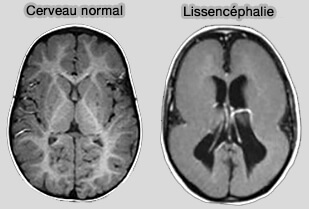

Remarque : Lis1 est le principal gène responsable de la lissencéphalie (" cerveau lisse "), maladie cérébrale grave associée à de nombreux symptômes dont des troubles cognitifs et une faible espérance de vie. Lis1 joue un rôle important dans le mouvement des noyaux neuronaux le long des microtubules et une bonne migration neuronale est essentielle pendant le développement du cerveau fœtal.